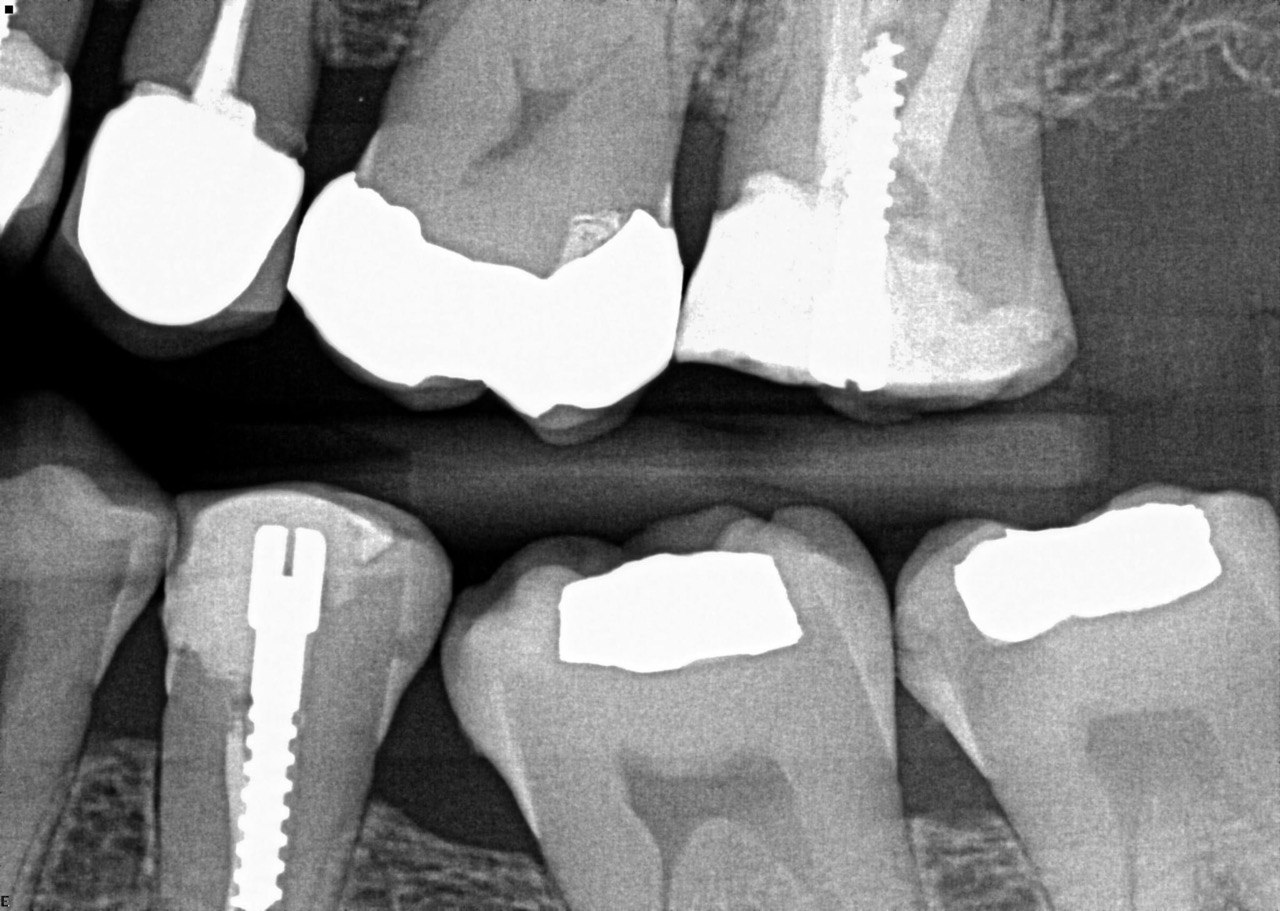

Question 5: Which surface shows recurrent caries?

Question 6: Which surface shows recurrent caries?

Question 8: What is the condition associated with the occlusal surface of the tooth # 1.6?

Question 9: What is the condition associated with the mesial and distal surfaces of the tooth # 1.4 respectively?

Question 10: What is the condition of the distal surfaces of the teeth # 1.5 and 1.6 respectively?